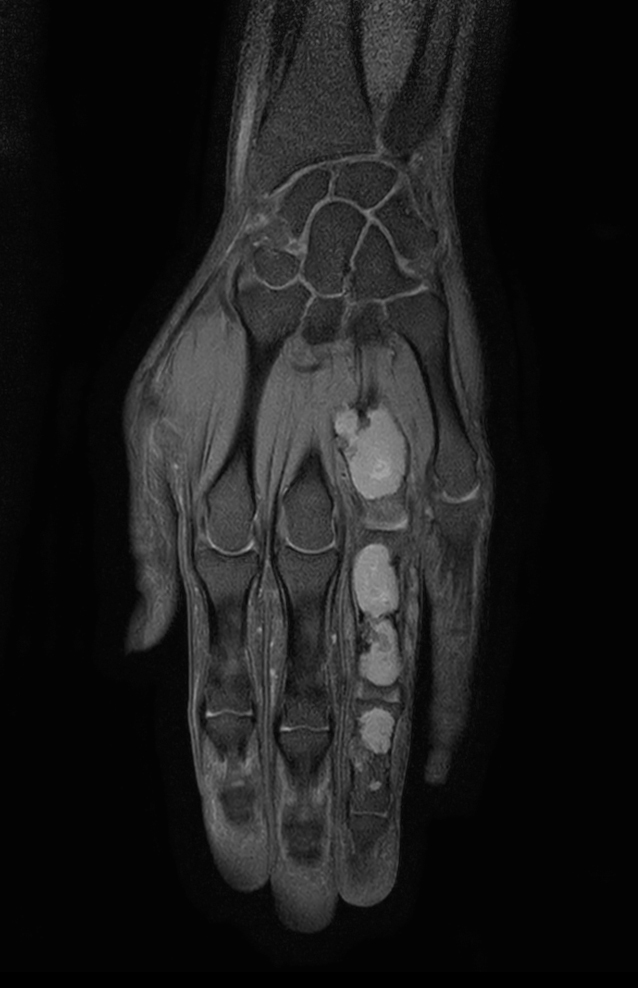

Hand/Wrist with tumor

Patient with a tumor in the hand region

Coronal T1w mDIXON XD TSE (Water only)